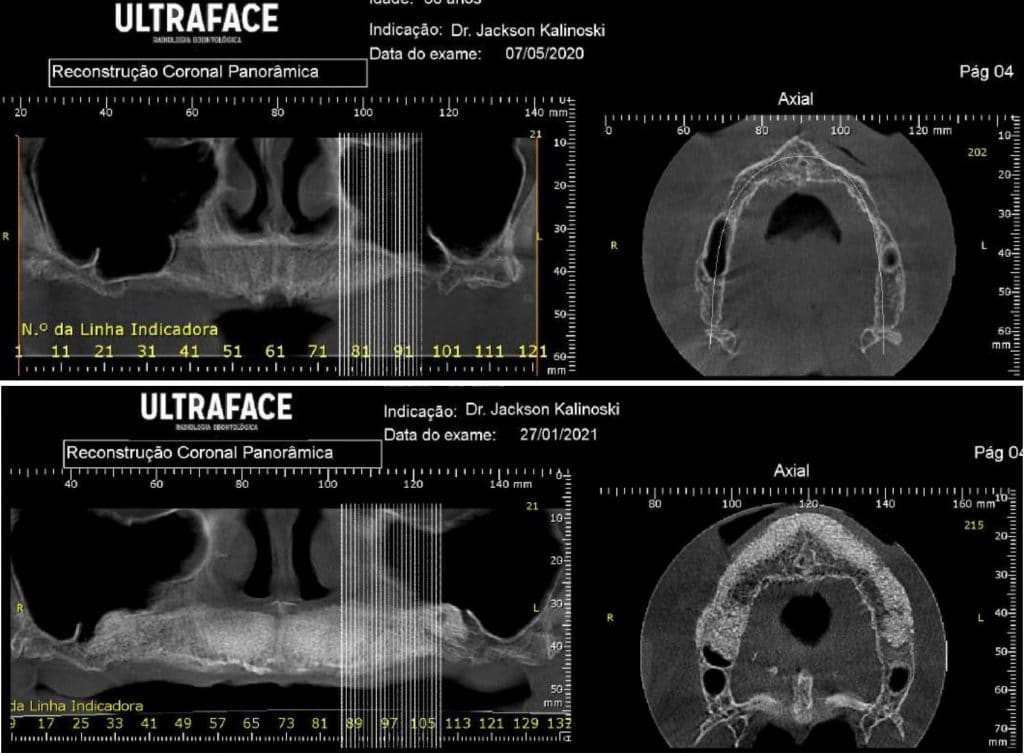

Olá colegas, aqui está um caso didático de reconstrução óssea total da maxila, levantamento do seio maxilar bilateral e bloqueio espesso com aplicação do conceito de PRF e Biotensigrity.

Após 6 meses de maturação óssea e implantes instalados com torque médio de 35 N / cm2.